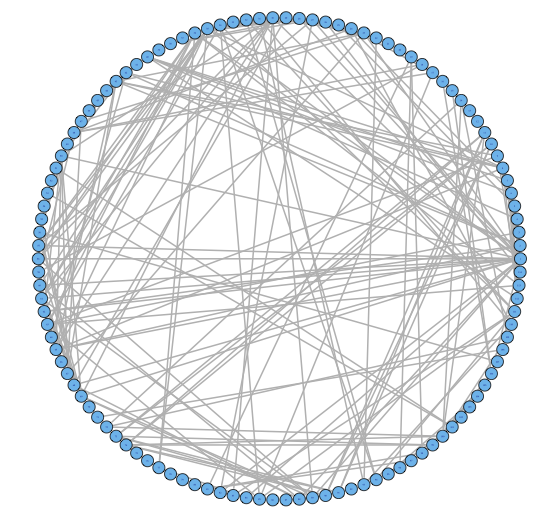

For our two-level problem (1.1.1), we must account for two sources of network variability when conducting population inference: (i) variability between subjects within a group and (ii) variability of the network selection procedure within a single subject. To see this, let us study a real multi-subject fMRI example. In Figure 2, we show estimated functional brain networks for subjects from the UCLA fMRI ABIDE data set INDI (2013). We describe the details of this data set, our pre-processing, and brain parcellation later in the Case Study in Section 5. In the top and middle panels, we estimate brain networks for each subject using graph selection methods for Gaussian graphical models (see Section 3.1 for details) and plot these as circle graphs to easily visualize network differences. It is clear that there are not only differences between autistic subjects and control subjects, but there is also large heterogeneity across subjects within each group. This is well-known in the neuroimaging literature (Milham et al., 2012; Nielsen et al., 2013), and makes finding statistically significant differences between subject groups much more challenging.

Less well studied in neuroimaging, is the second source of variability which arises from estimating networks for each subject instead of directly observing the networks. In the bottom panel of Figure 2, we re-estimate brain networks for a single control subject with bootstrap resampled data. It is clear that there is major intra-subject variability arising from our graph selection procedure. Indeed in neuroimaging, test–re-test studies which conduct brain imaging on the same subject in repeated sessions have shown high variability in the subject’s estimated brain networks (Wang et al., 2011). This also motivates the necessity of using a two-level model like (1.1.1) for population network inference as opposed to the one-level model and test statistics of the standard procedure.